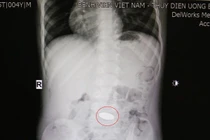

Các bác sĩ Bệnh viện Sản Nhi tỉnh Vĩnh Phúc đã gắp thành công một đồng xu kim loại có hình tròn đường kính 3cm từ trong thực quản cháu bé 4 tuổi ra ngoài.

BVĐK Xuyên Á vừa tiếp nhận bé gái 2 tuổi nuốt phải chiếc nhẫn vàng đeo trên ngón tay, khiến dị vật trôi vào thực quản, gây khó thở, sặc sụa. Một bé trai khác 4 tuổi cũng phải cấp cứu vì hóc đồng xu…

Trong lúc cầm chơi đồng xu, bé L. 5 tuổi (bé gái), ngụ tại huyện Hóc Môn, TPHCM đã bỏ đồng xu vào miệng và bị mắc tại thực quản, được các bác sĩ của Trung tâm Nội soi BV Đa Khoa Xuyên Á gắp ra thành công – TS.BS Nguyễn Văn Châu, Tổng Giám đốc BV Đa khoa Xuyên Á vừa cho biết.